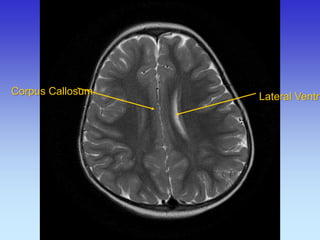

Corpus Callosum

Thalamus

Lateral Ventricle